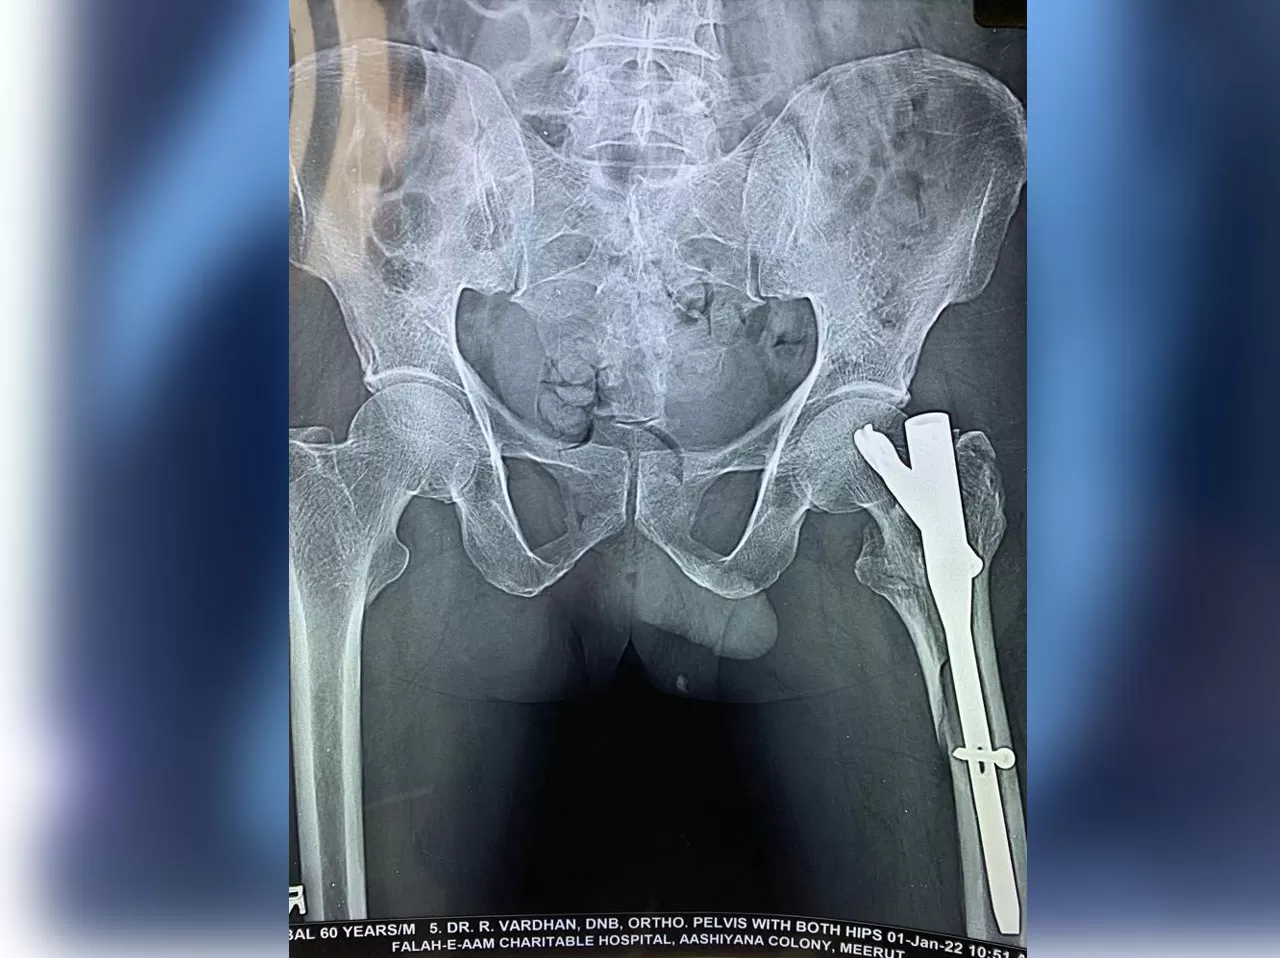

Mr. Iqbal

Name: Mr. Iqbal

Date of Operation: 31 Jan 2022

Age: 65 Years